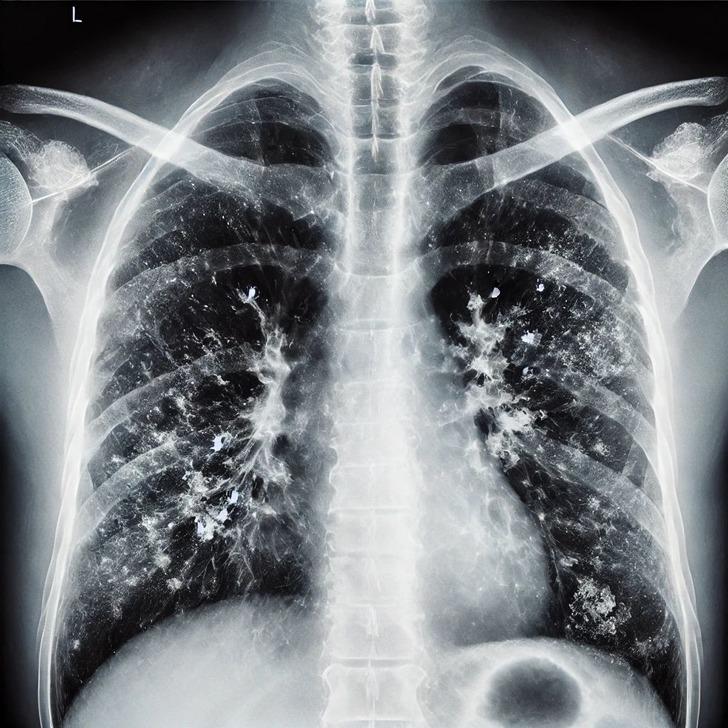

Zatürrenin grip ya da soğuk algınlığıyla karıştırılabileceğini belirten Prof. Dr. Özlü, "Bu tür enfeksiyonlar genelde üst solunum yollarında yerleşir. Oradan başlar ve nezle, soğuk algınlığı, farenjit, sinüzit gibi üst solunum yolu enfeksiyonlarına yol açar. Bazen de alt solunum yollarına ilerleyerek bronşit, bronşiolit gibi hafif hastalıklara yol açabilir. Fakat zatürre, bu hastalıklar arasında en ağır olanıdır. Maalesef, şu sıralar pek çok hasta zatürreyi fark edemiyor ve teşhiste geç kalıyor. Oysa zatürrede erken tanı çok önemli. Hekimin, 4 saat içinde doğru tedaviye başlaması, zatürreye bağlı ölümleri anlamlı şekilde azaltıyor" ifadelerini kullandı.

Zatürre ve soğuk algınlığı arasındaki farklara dikkat çeken Özlü, "Şöyle ki; 'Zatürre mi, soğuk algınlığı mı?', 'Zatürre mi, yoksa bronşit gibi bir alt solunum yolu enfeksiyonu mu?', bu ayrımın yapılması lazım. Bu ayrımı bir göğüs hastalıkları uzmanı yapabilir. Ancak hastalar, 'Ben zatürre olup olmadığımı nasıl anlarım?' diye soruyor.

Aslında tüm solunum yolu enfeksiyonlarında; ateş, halsizlik, kırgınlık, boğaz ağrısı, öksürük, burun akıntısı, geniz akıntısı, burun tıkanıklığı gibi semptomlar olabilir. Ancak zatürrede bu şikayetlerin çok daha ağır seyrettiğini biliyoruz. Ateşiniz çok yüksekse, üşüme ve sıtma nöbetleri oluyorsa, aşırı bir takatsizlik ve bitkinlik durumu varsa, genel sağlığınızı bozuyor, yeme ve içmenizi aksatıyorsa zatürre olma olasılığı yüksektir" diye konuştu.

Zatürre tanısında en önemli belirtilerin nefes darlığı ve öksürük olduğunu ifade eden Özlü, "Şikayetleriniz tedaviyle ya da tedavisiz olarak ilk birkaç gün içinde azaldıktan sonra tekrar ikinci bir atak yaşanıyorsa; ateşlenme ve şikayetlerde artış oluyorsa bu da zatürrenin eklendiğini gösterebilir. Nefes darlığı çok önemli bir belirti. Özellikle nefes alıp vermekte zorlanıyorsanız, özellikle bebeklerde ve yaşlılarda solunum sayısının dakikada 24'ün üzerine çıkması, nefes alıp verirken hırıltı olması, bebeklerde burun kanatlarının solunuma eşlik etmesi, nabız sayısının dakikada 120'nin üzerine çıkması gibi durumlar zatürre olasılığını güçlendirir.